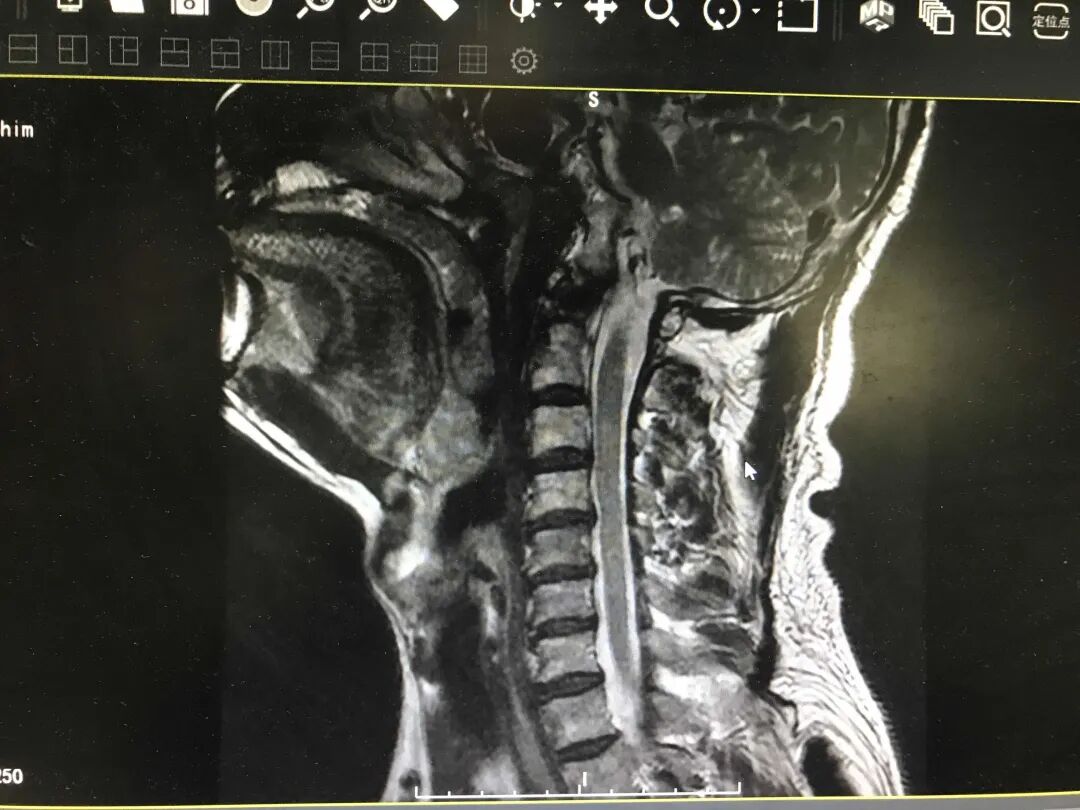

最近,48岁的邓大哥已经连续几天没睡一个好觉了,其颈部及左上肢疼痛明显,无法仰卧也不能俯卧,只能勉强右侧卧位,严重影响睡眠和正常生活。

张燕伟主任结合相关检查,辨证诊疗,采取针刺、推拿、拔罐等治疗方法以疏经通络止痛。